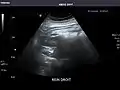

Right kidney

Kidneys: Right and left kidneys measure 11.5 cm and 12 cm in length respectively. No hydronephrosis. Small left lower pole kidney cyst.